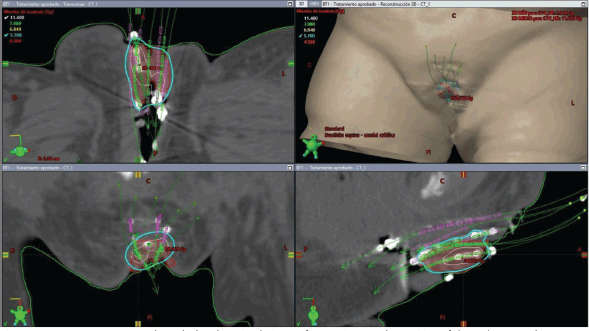

The initial plan suggested possible undercoverage in superficial regions of the tumour (Figure 3). Therefore, a custom silicone bolus containing four additional catheters was placed on the vulvar surface to enhance coverage of peripheral edges. A repeat CT confirmed improved D100 and D90 of the GTV while maintaining urethral dose constraints (Table 1, Figure 4).

Figure 3. Case 1. 3D treatment plan calculated on simulation CT for fraction #1. The position of the catheters and the dosimetric distribution in the axial, coronal and sagittal planes are observed, in addition to a 3D reconstruction. In light blue, the isodose of 5.7 Gy; in white, the isodose of 11.4 Gy.

Figure 4. Case 1. 3D treatment plan with bolus. The position of the catheters and the dosimetric distribution in the axial, coronal and sagittal planes are observed. On the left, fraction #2 to #5. On the right, fraction #6 to #8. In light blue, the isodose of 5.7 Gy; in white, the isodose of 11.4 Gy.